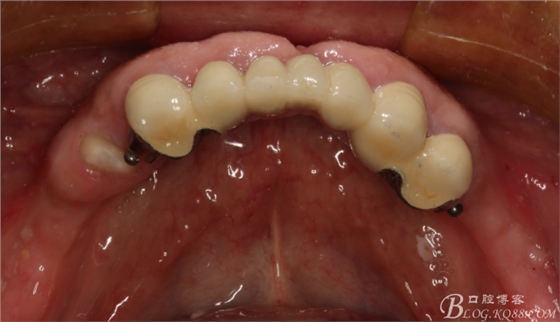

下頜由于44治療之后,松動(dòng)度改善不大,原來的咬合創(chuàng)傷比較大,不能承擔(dān)較大的(牙合)力,選擇覆蓋義齒,把它磨短平齊牙齦,

其他牙比較集中,選擇雙端球帽式附著體修復(fù)雙端游離缺失

修復(fù)后效果圖,